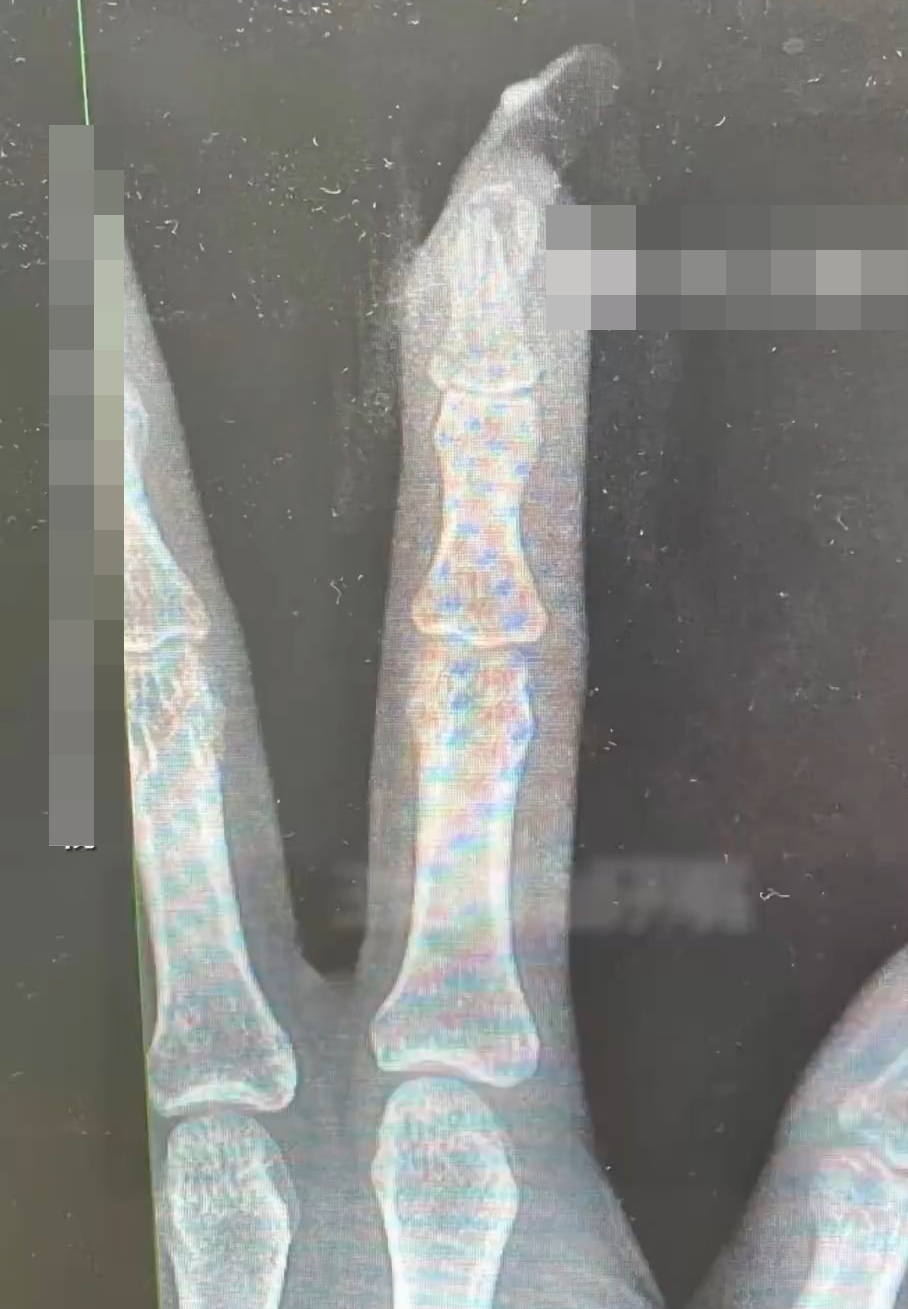

做了美甲後的王女士跌倒,手指骨出現折斷。九派新聞

王女士後來到醫院求診,接診的骨科醫生曹立檢查後發現王女士「食指指骨骨折,甲床破裂。」由於指甲斷裂,部分甲床外露,需要手術修復。

曹醫生曹醫生坦言,如果沒有美甲,傷害不會這麼嚴重。經過指骨骨折閉合復位內固定術,王女士傷勢恢復良好。